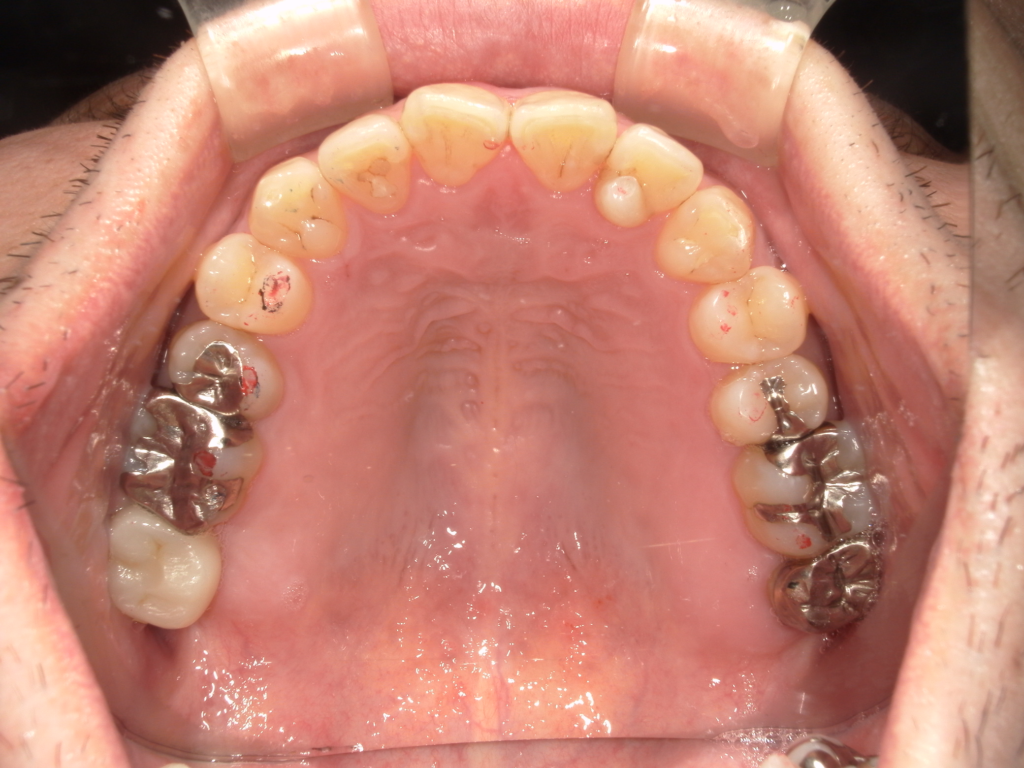

Y様インプラント実例 #44

左の上下の奥歯をインプラントで治療しています。

左下の奥歯は歯を抜くのと同時にインプラントの埋め込みを行っています。

被せものは上下、セラミックスで作っています。

治療前

治療後